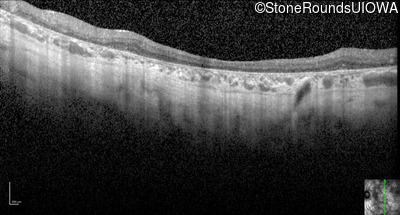

Optical Coherence Tomography - Right - 10/100 -2

Exemplar / OCT Stack